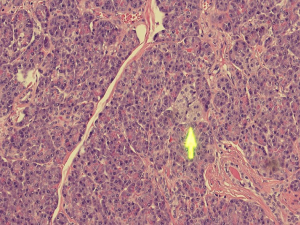

Histopathological analysis of the specimen revealed complete excision of the mass, which was reported to be benign pancreatic tissue, showing both endocrine and exocrine elements (islets of Langerhans, pancreatic acini, and pancreatic ducts) (Figures 4-9). No atypical features were seen and there was no evidence of malignancy.